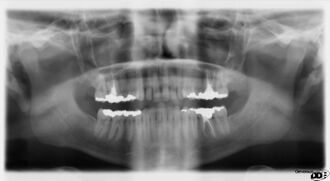

Panoramic radiograph

Panoramicfilm.JPG

A dental panoramic radiograph, showing the maxilla and mandible, all the teeth including the "wisdom teeth," the frontal and maxillary sinuses, the nasal cavity and the temporomandibular joint and other near by head and neck anatomy.